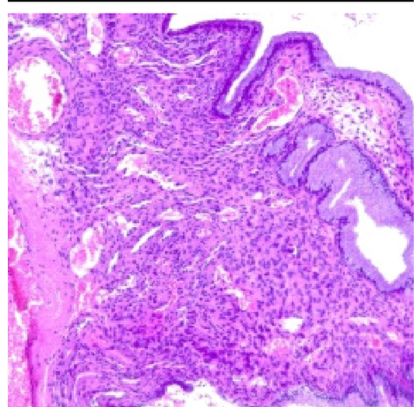

D. Biopsja i badania histopatologiczne

- W przypadku podejrzenia polipa szyjki macicy, lekarz może zdecydować się na pobranie próbki tkanki (biopsję) w celu dalszej analizy histopatologicznej.

- Badanie histopatologiczne pozwala na dokładną ocenę zmian tkankowych, umożliwiając postawienie precyzyjnej diagnozy i wykluczenie ewentualnych powikłań.

Przeprowadzenie kompleksowej diagnostyki polipów szyjki macicy, obejmującej badania ginekologiczne, cytologię, kolposkopię, USG transwaginalne, biopsję i badania histopatologiczne, pozwala na skuteczne zidentyfikowanie oraz monitorowanie polipów i ich ewentualne leczenie, przyczyniając się do zachowania zdrowia i dobrostanu pacjentki.